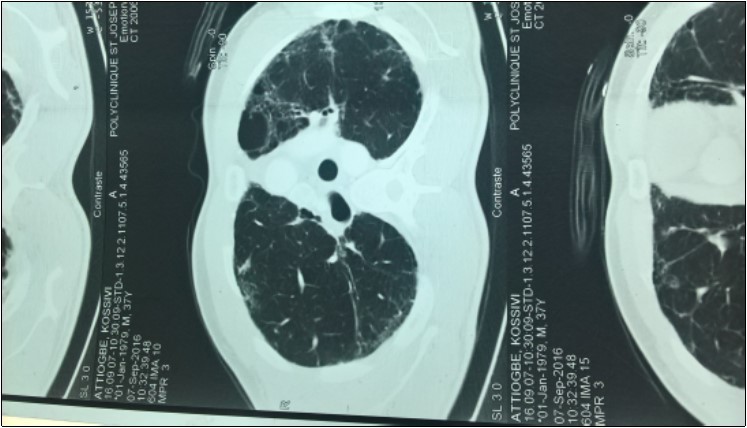

Mr ATT Kos is a 44-year-old patient receiving neurological consultation for dyspnea and sensation of generalized muscle weakness worsening on exertion. The onset of the symptoms dates back to August 2005 marked by the progressive installation of a dyspnea of effort without the notion of cough or slimming. There was no associated infectious context. A consultation in pneumology made it possible to classify his dyspnea at stage I of Sadoul. After a chest radiograph that was normal, he had a thoracic CT scan that revealed multiple bubbles of bilateral emphysema. The patient was then given corticosteroids and beta 2 mimetic. The development was marked by a discreet improvement in dyspnea. The patient again consults with the persistence of dyspnea and a fatigability to the usual effort with modification of the timbre of the voice. This consultation made on December 29, 2016 had made it possible to find episodes of rare false roads as well as a ptosis in case of extreme fatigue. Clinical examination was normal. The diagnosis of myasthenia gravis was then discussed. The detection of anti-receptor anti-acetylcholine antibodies (Ac Anti RACH) was positive with a titre of 0.8 nmol / ml (normal less than 0.2 nmol / ml.) The electromyogram showed a moderate decrease in motor potential at The repetitive stimulation was of the order of 9% .The mediastinum scan showed bilateral pulmonary fibrosis (Figure 1) in relation to its progressive pulmonary pathology and a prostigmine test was performed during a fatigue episode associated with A ptosis and a marked regression of the signs The examination of the patient by a pulmonologist revealed that his present dyspnoea was in Stage II of SAOUL Spirometry reported a 52% FVCI, 63% FEV 1 EFF To 118%, with no improvement in the beta 2 mimetic parameters, and the gasometric data were: PaO2 = 59%, PaCO2 = 54%, PH = 7.39 Hb = 14.3 and HCO3 = 32 The association of myasthenia gravis and fibrosis Motivated by the search for antinuclear antibody: negative; Anti-tRNA-synthetase antibody: positive for anti-PL7 and negative for anti-PL12; Negative also for anti-EJ and anti-OJ. Anti-KU and anti-Pm / Scl antibodies were also negative. Anti-synthetase syndrome has been retained in our patient. It was then placed on Pyridostigmine at progressive dose and Prednisolone at degressive dose. This treatment allowed a stabilization of the clinical state of the patient.